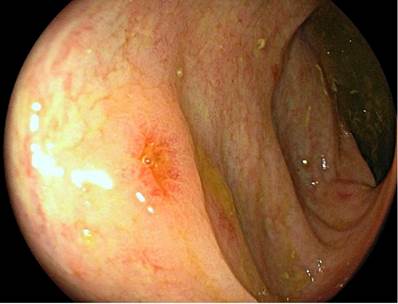

Por medio de una colonoscopia se accedió al íleon y se encontró atrofia difusa de la mucosa, ausencia de vellosidades, además de marcada friabilidad con sangrado fácil y esfacelación al roce, sangrado moderado e inclusive formación de pequeños hematomas submucosos a la toma de biopsias (Figura 2). La mucosa colónica se encontraba normal. El estudio histopatológico de las biopsias tanto de duodeno como de íleon permitió confirmar el diagnóstico de EICH agudo grado 4/4 (Figura 3). La evolución del paciente fue tórpida con persistencia de la diarrea, alto gasto fecal, sangrado digestivo, desórdenes hidroelectrolíticos de difícil manejo, múltiples transfusiones de hemocomponentes, desarrollo de bacteriemia por Klebsiella pneumoniae y falla respiratoria hipoxémica. Se consideró que cursó con EICH aguda, grave y refractaria a esteroides, con criterios de mal pronóstico, y cuyo desenlace fue la muerte 56 días después de la hospitalización.

Se presenta el caso de un paciente masculino de 17 años con diagnóstico de linfoma linfoblástico T, que recibió inicialmente terapia de inducción y reinducción con protocolo GRAALL Lysa (citarabina + idarrubicina) con la que se logró la remisión de su enfermedad. Fue llevado a trasplante haploidéntico de progenitores hematopoyéticos con su padre como donante. Durante el proceso de trasplante desarrolló exantema macular difuso, de predominio en las extremidades. La biopsia de piel confirmó el diagnóstico de EICH aguda con compromiso cutáneo grado 3/4. Al día 32 del trasplante comenzó a presentar fiebre, dolor abdominal en el hipogastrio y ambas fosas ilíacas, además de deposiciones líquidas sin moco ni sangre. La tomografía axial computarizada (TAC) de abdomen documentó cambios inflamatorios de la región ileocecal y signos de ileítis terminal, razón por la cual se solicitaron estudios endoscópicos y en la EGD se encontró eritema plano en parches en el estómago, sin cambios inflamatorios en el duodeno. En la colonoscopia se halló mucosa del íleon congestiva con múltiples úlceras, superficiales, irregulares, de bordes planos y superficie lisa; además, en todos los trayectos colónicos incluyendo el recto se evidenciaron pequeñas úlceras puntiformes con fibrina en el centro y bordes planos congestivos (Figura 4). El estudio histopatológico confirmó el diagnóstico de EICH aguda en el íleon grado 3/4, colon derecho 1/4, colon izquierdo 3/4 y recto 4/4 (Figuras 5 y 6). La inmunohistoquímica (IHQ) sobre estas muestras fue negativa para citomegalovirus (CMV).